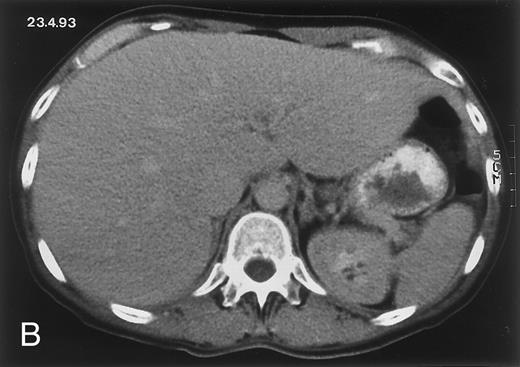

Radiologic evolution in patient A. (A) Postcontrast abdominal CT scan on March 16, 1993 shows multiple small hypodense areas in all segments of the liver, suggestive of hepatic candidiasis. Seven days previously, the patient had recovered from severe neutropenia after the first cycle of chemotherapy for AML. (B) On April 23, 6 days after the neutrophil count had dropped below 500/μL in the second cycle of chemotherapy, there is no evidence of focal lesions on postcontrast CT scan. (C) On June 18, when neutrophils were normalized for 46 days, CT scan again shows multiple small abscesses.

Evolution of fungal lesions on CT scans during and after neutropenia is summarized in Table 2. Figure 1 (patient A) and Fig 2 (patient B) serve to illustrate Table 2.

In three patients, multiple round lesions were seen on postcontrast CT scans of the abdomen in the liver and the spleen, while in two cases, lesions could only be seen in the liver (Table 2). Following the diagnosis of disseminated candidiasis, these lesions decreased in size and visibility during subsequent neutropenia in three patients (compare Fig 2A and B) and disappeared completely in two patients (compare Fig 1A and B). The numbers of days of severe neutropenia (neutrophils <500/μL) at the time the CT scan was performed are listed in Table 2. After recovery from neutropenia and despite continued antifungal therapy, the size and visibility of the lesions increased again (Fig 1C). Similarly, the number of days since recovery from severe neutropenia (neutrophils >500/μL) are listed in Table 2. In two of three patients treated with another cycle of myeloablative chemotherapy, this waxing and waning pattern of radiologic lesions could be seen again (Fig 1D and E). In all patients, lesions eventually disappeared (Figs 1F and 2D) after prolonged antifungal therapy.